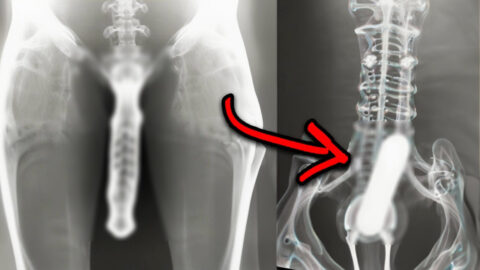

StoriesList 15 Strangest Things Discovered By X-Rays Imagine going in for a routine checkup only to find out that there’s something not so routine lurking inside of you. X-rays have uncovered the most bizarre and unbelievable things 1 year agoKeep Reading